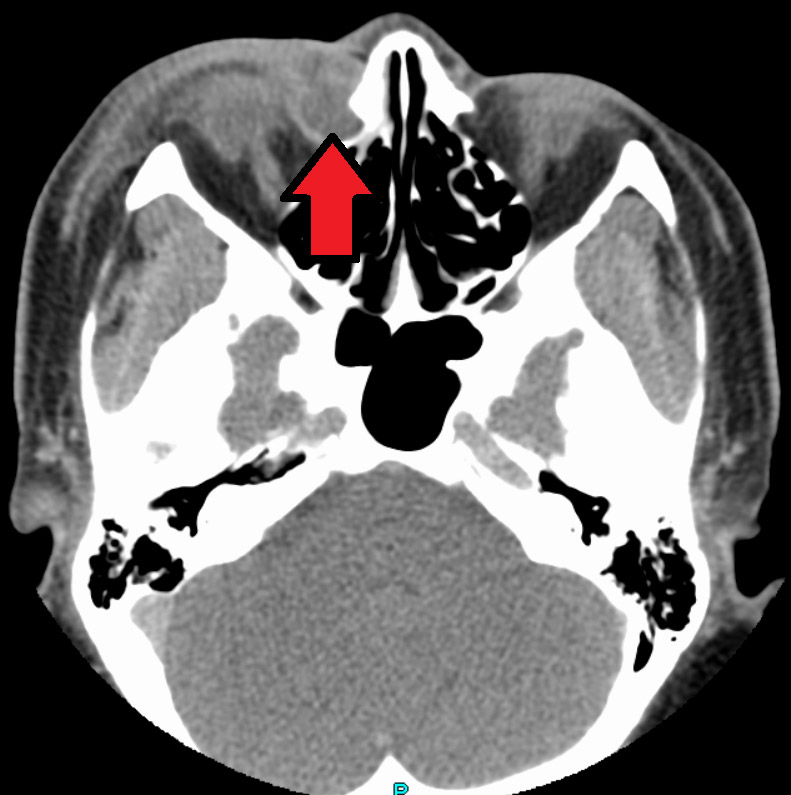

Dacryocystitis is an infection of the tear sac that lies between the inner corner of the eyelids and the nose. It usually results from blockage of the duct that carries tears from the tear sac to the nose.

Detection and Diagnosis

During the examination, the eye care practitioner will determine the extent of the blockage. Cultures may be taken of the discharge to identify the type of infection. The eye care practitioner will also determine whether the infection has affected the eye.